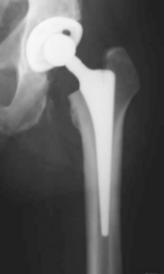

Bei den totalen Hüftendoprothesen (Hüft-TEP) werden in der Regel eine künstliche Hüftpfanne und eine Schaftprothese mit Aufsteckkopf implantiert. Hierfür stehen unterschiedliche Prothesenmodelle und Verankerungsmöglichkeiten (zementiert, zementfrei) zur Verfügung. Eine neuere operative Versorgungsmöglichkeit stellt der Hüftoberflächenersatz dar. Es handelt sich hierbei um ein besonders knochensparendes Prothesensystem, dessen klinischer Einsatz jedoch noch jung ist, sodaß potentielle Vorteile noch nicht abschließend beurteilt werden können.

Bei der zementierten Hüftprothese wird eine anatomisch angepasste Schaftprothese aus einer hochwertigen Edelstahllegierung (CoNi) über Knochenzement in der Markhöhle des Oberschenkelknochens verankert. Der Gelenkpartner zur künstlichen Hüftpfanne besteht in der Regel aus einem Keramikaufsteckkopf.

Als Pfannenersatz wird bei diesem Verfahren eine aus Polyethylen

bestehende Pfannenschale durch den Knochenzement im zuvor aufbereiteten

Pfannenlager befestigt. Vorteil der zementierten Hüftprothesen ist die

jahrelang zurückreichende Erfahrung mit diesen Systhemen, die sich zum

Teil über Jahrzehnte bewährt haben.

Bei der zementfreien Hüftprothese besteht die Schaftprothese aus einer speziellen Titanschmiedelegieung, welche das Anwachsen von Knochen fördert. Den Gelenkpartner zur künstlichen Hüftpfanne bildet ein Aufsteckkopf aus Keramik.

Als

Pfannenersatz wird in das zuvor aufbereitete Pfannenlager eine

subhemisphärische Titanschale eingepresst oder geschraubt, in welche

dann spezielle Polyethylen- oder Keramik-Inlays eingebracht werden.